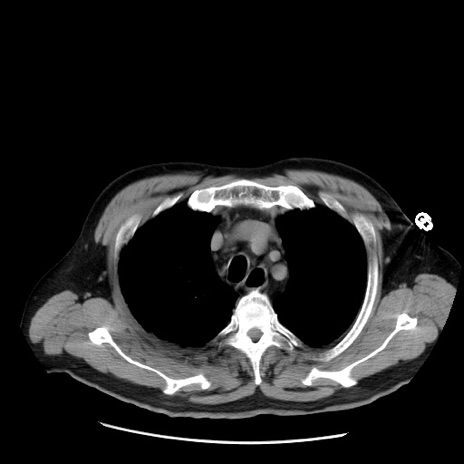

症例20(横断像)

【症例】 60歳代男性

【主訴】 腹部膨満、嘔吐

【現病歴】5日前頃より倦怠感を認め食事量減少し4日前の朝嘔吐、食事摂取困難となった。 3日前近医受診し点滴施行され整腸剤などを処方された。 当日他院を受診し、腹部膨満著明、炎症反応の上昇(CRP10.8、WBC11200)あり、紹介受診となる。

【身体所見】 意識JCS1 受け答えがはっきりしないBP 111/57mHg、 P 67bpm、、BT35.2°C、SpO2 97%(RA)、 腹部:膨隆、打診で鼓音あり、全体的に圧痛有り、腸蠕動音(-)、反跳痛ははっきりせず。

【データ】WBC 11400、CRP 14.20